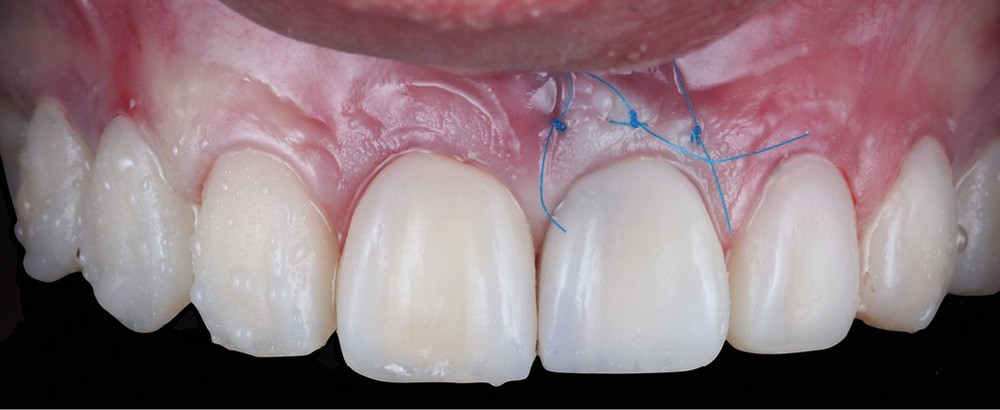

Acte 6 : assemblage et résultat (fig. 9 et 10)

Nous assemblons les céramiques selon la technique choisie (scellement pour les couronnes et collage pour les facettes). Le patient est revu à quinze jours pour contrôle de la cicatrisation.